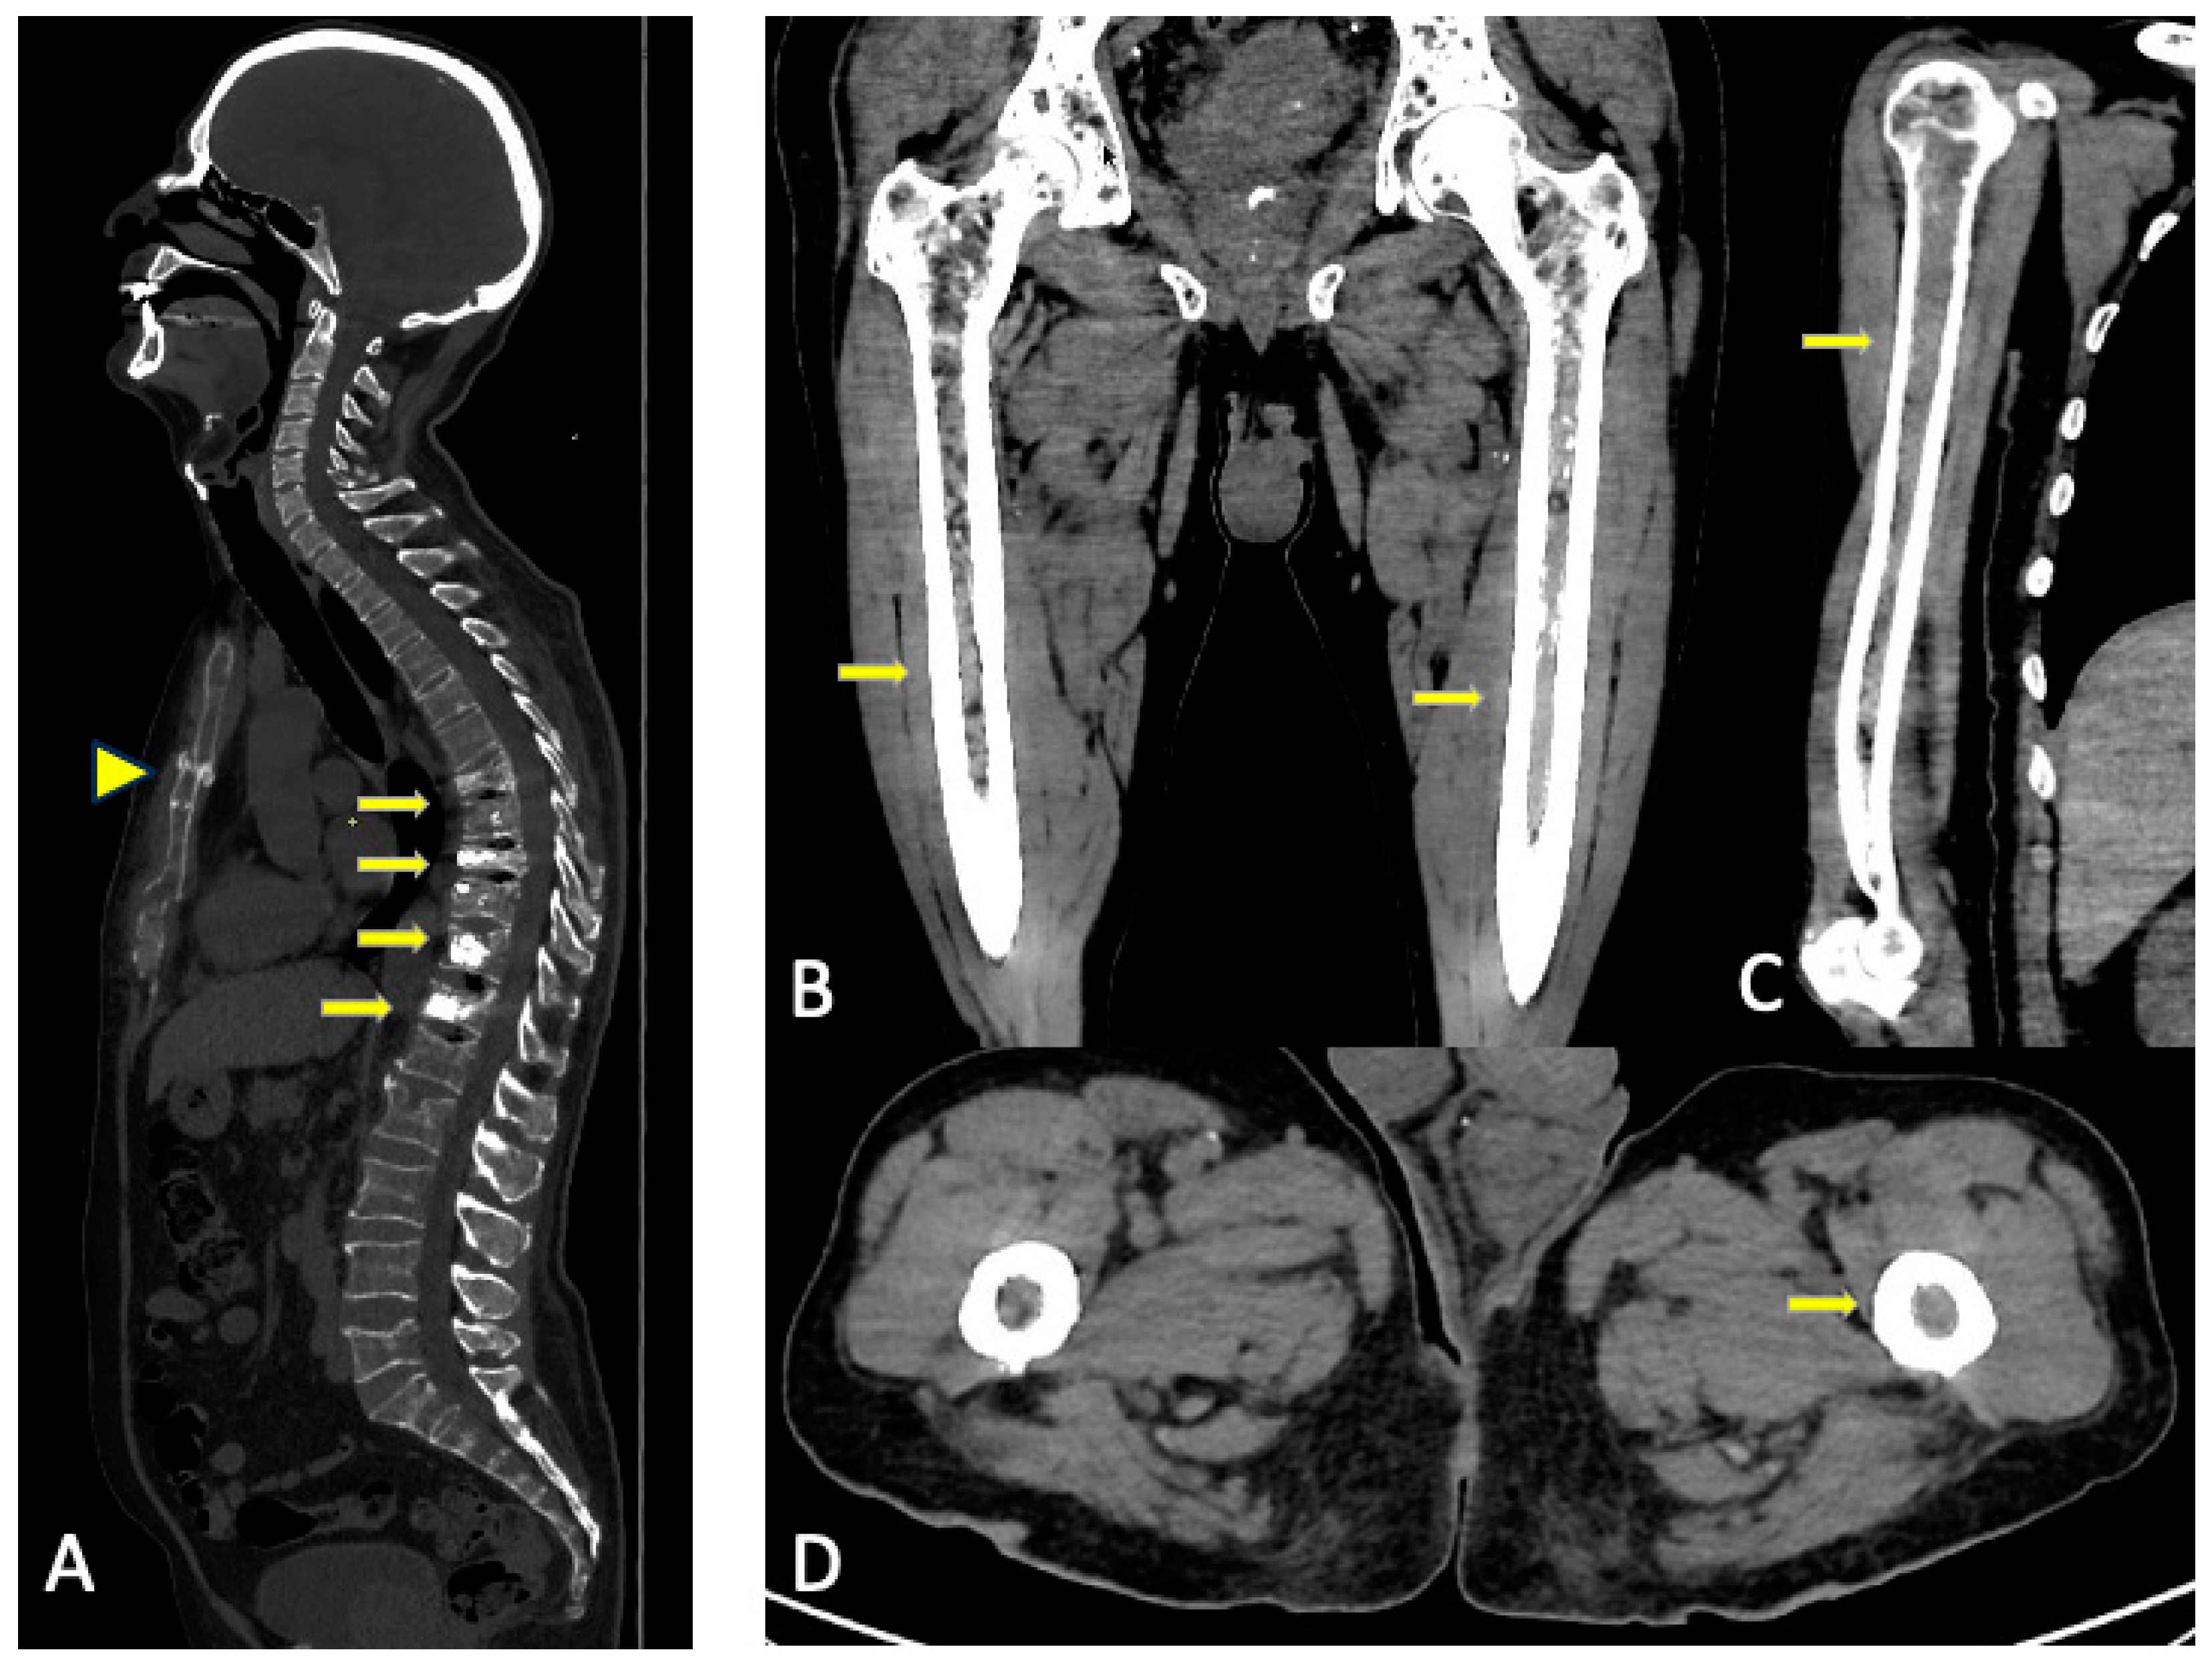

3. WBLDCT

3.2. Imaging Findings